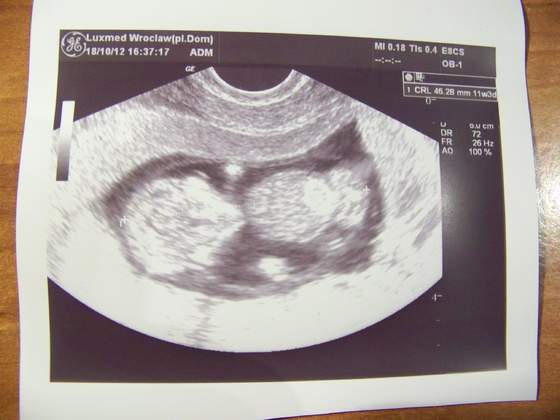

Ja już po wizycie, dzidzia rośnie jak powinna i jest wszystko w porządku. Ułożyła się tak, że doktórka nic nie dostrzegła czy coś tam dynda czy nie

Termin z USG to 1.05.2013 czyli ledwo się łapię na majóweczkę.

Dołączam zdjęcie mojego 4,5 cm szczęścia.